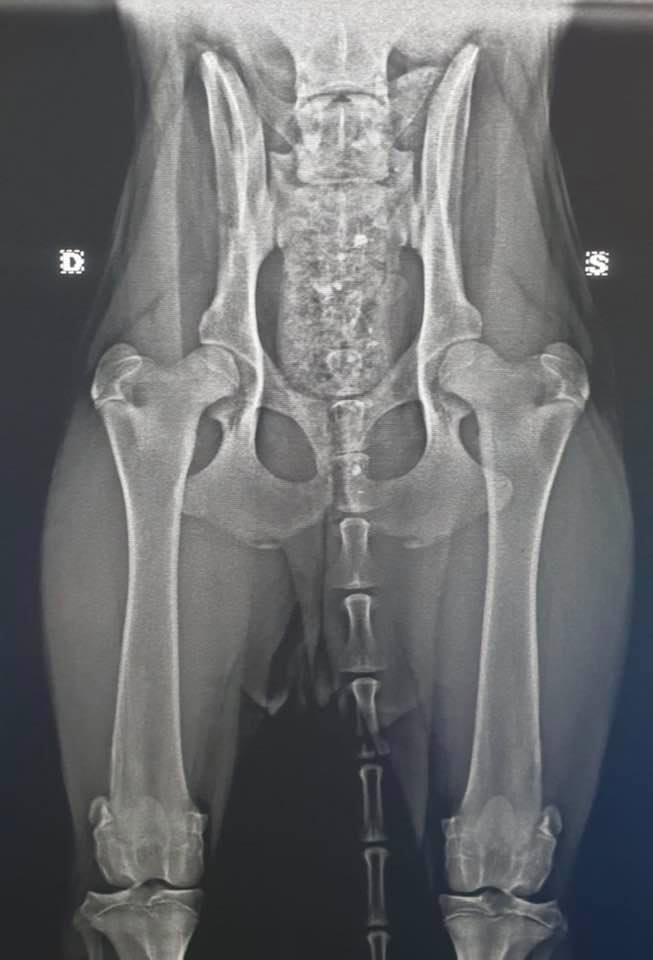

Wer hier auf dem Bild sagt, das geht doch noch, der solle sich doch mal hinsetzen und noch zu den vielen Punkten, nehmen wir mal den Kreuzbandriss als Beispiel an, folgendes hinzurechnen. Kostender OP 2.000 + 4facher Satz an Gebührenordnung + evt. Not Op am Wochenende + Tagesaufenthalte für eine Woche in der Klinik inkl. Medikamentensetzung und Heilmittel, Wundversorgung und Physiotherapie, nach Entlassung, dreimaliges vorstellen inklusiver Nahtversorgung, Medikamentgaben für zuhause und Verordnung von wochenlanger Physiotherapie usw.

Summe kommt dann all inklusive auf rund 5000 Euro, wenn alles glatt verheilt. Hat das jemand sofort in der Tasche an den Normalos an Hundehaltern? Ich nicht und tausende andere auch nicht.